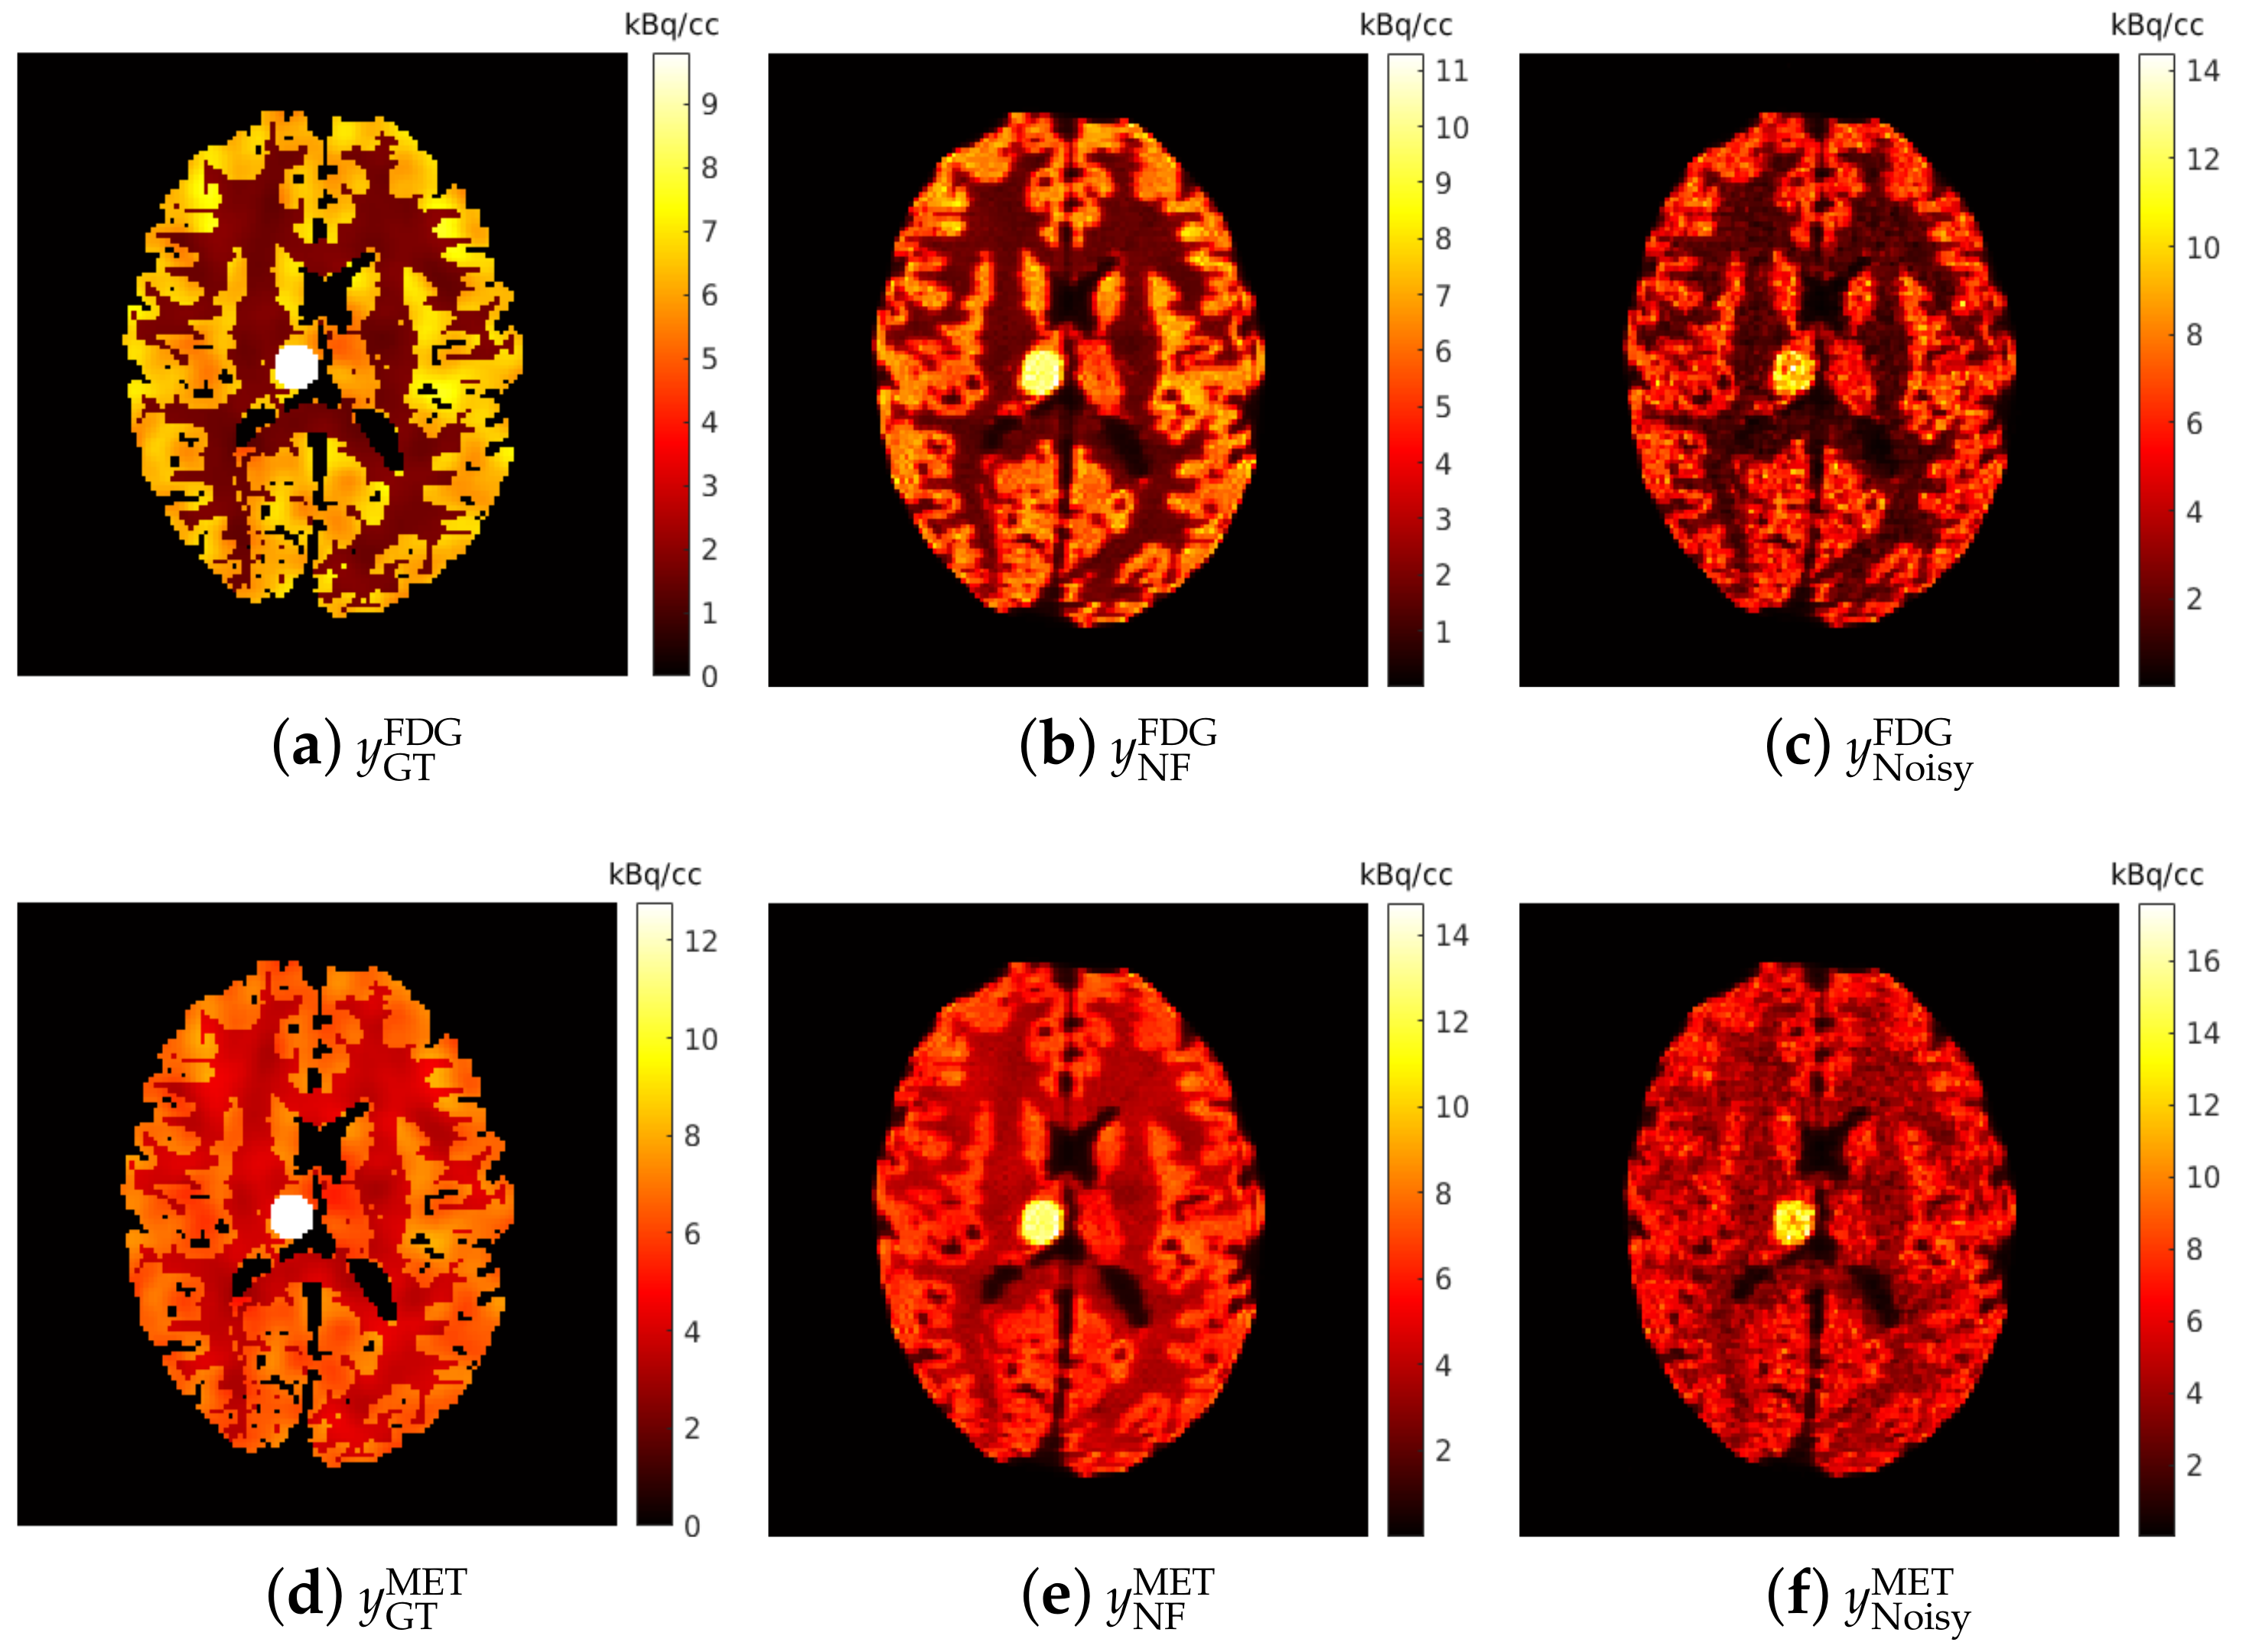

Figure 7 shows for each that the average NRMSE decreases and that a smaller SD is obtained in the test set as the number of training pairs increases from 1 to 80. This is consistent with the visual impression of the separations obtained by the DL-based method, as shown in Figure 8 and Figure 9. The first to fifth columns display the separated static single-tracer images (activity distributions) based on different numbers of training pairs (for plotting only, we limit the colour scale of the figures to fall within the same range as the reference images in Figure 6b for and Figure 6e for , respectively). Although all cases successfully recover the separated images, using more training pairs results in higher separation performance in terms of recovering the tumour regions, shapes and low contrast of the white and grey matter for . Figure 10a,c also suggest that the more training pairs used, the better the average NRMSE, which is in line with the results shown in Figure 7. With 80 training pairs, the DL-based method achieved average NRMSE values for FDG and MET of ∼15% and ∼12%, respectively, for the test set across all (see the magenta lines in Figure 10a,c).

Figure 9.

Brain phantom (whole brain region): the static images recovered using the DL-based method (Columns 1 to 5) and the CM-based method (Column 6).

A test example of the separated images using the CM-based method is shown in the last column of Figure 8 (FDG) and Figure 9 (MET) for different . Compared to the results obtained from the DL-based method, the separated images using the CM-based method are much noisier because the model fitting (4) may fall into local minima even when the noise level is low. Although several strategies, such as using differing initial values or an exhaustive search algorithm [22], have been suggested to reduce local minima, their use in clinical practice is challenging because of their high computational cost.

4.3. DL-Based Method and CM-Based Method Comparison

The separation results between the DL-based method and CM-based method applied to the reconstructed dynamic dual-tracer noisy MLEM images were compared. For = 0, 5, 10 and 15 min, Figure 8 and Figure 9 show that in terms of visual assessment the CM-based method produces much nosier separated images than the DL-based method. This observation is consistent with better average NRMSE values of the DL-based separation results as illustrated in Figure 10. When using only 1 training pair, the DL-based method achieved high average NRMSE values across all (∼25% for FDG and ∼22% for MET). However, it nevertheless produces better average NRMSE values for = 0, 5, 10 and 15 min when compared to the separation results using the CM-based method. In fact, there are TACs contained in 1 training pair, one for each voxel; hence, in this instance, the proposed network was trained using TACs. Note that the DL-based method utilises both spatial and temporal information of the TACs from all voxels, but the CM-based method was implemented voxel by voxel, meaning only temporal information of one TAC was considered at each time. Therefore, for = 0, 5, 10 and 15 min, the DL-based method with 1 training pair yields better separation performance. When = 2 days, the CM-based method, in contrast to the DL-based method with 80 training pairs, achieved lower average NRMSE values for both FDG and MET. We believe this is the result of not enough training data which includes the case of = 2 days.